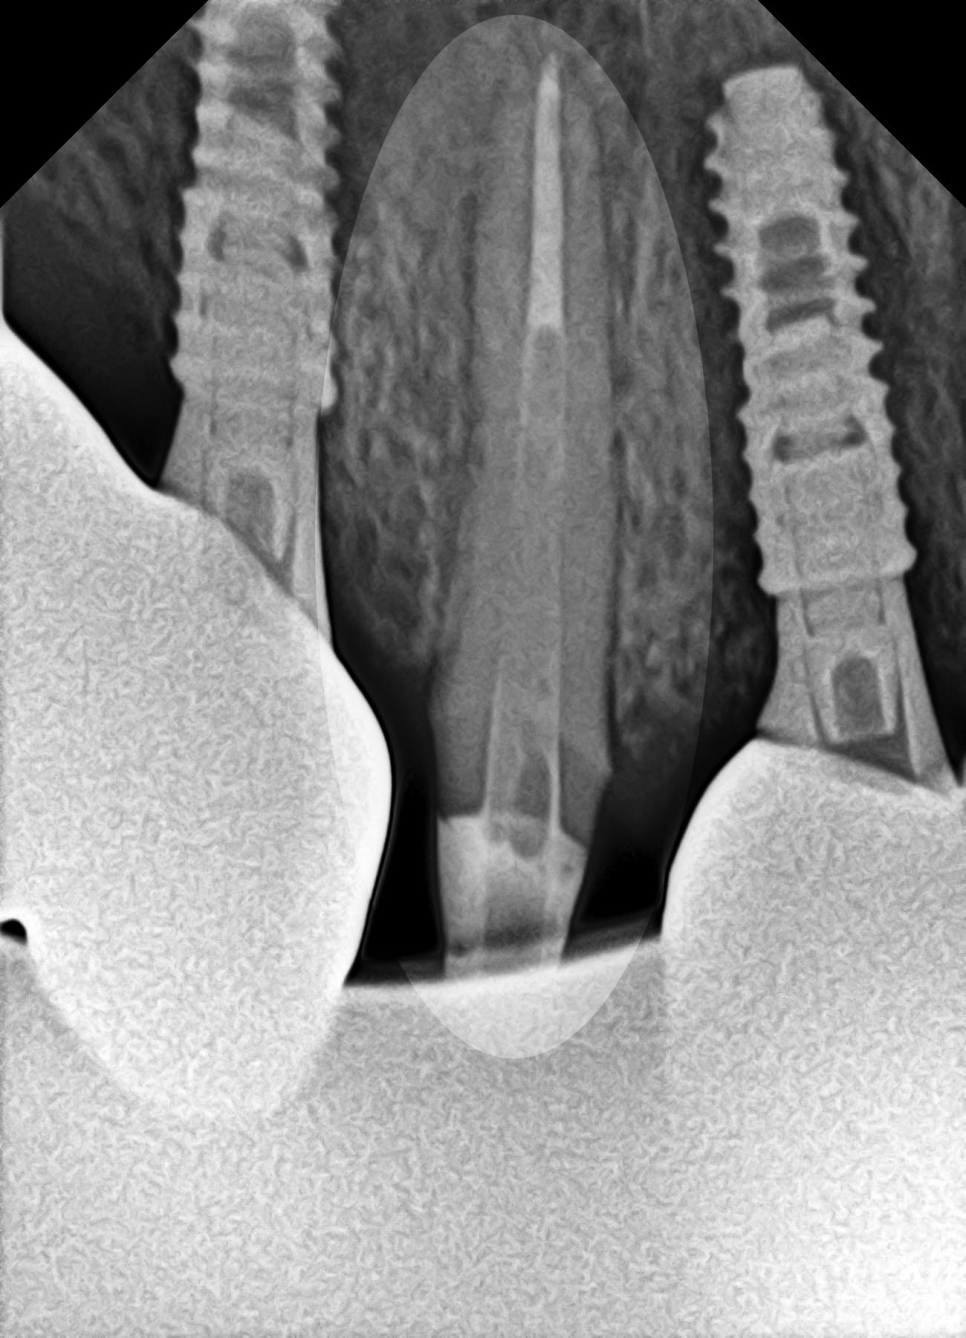

사진처럼 치아머리 부분이 온전히 파절된 경우,

그대로 보철을 씌우기엔 한계가 있습니다.

보철과 지대치가 연결되는 부분이

어느 정도 확보되어야 유지에 별다른

문제가 없기 때문이죠.

잇몸 윗쪽으로 지대치가 어느 정도

확보될 수 있도록 [치관확장술]을

적용해 볼 수 있습니다.

잇몸을 절개하여 치아머리 부분을 확보하는 시술로

지금처럼 파절된 범위가 넓을 때 적용해 볼 수 있으며,

앞서 당산동 치과 에서 설명드린 치관확장술 과정을 통해

앞니 머리 부분 지대치를 어느 정도 확보한 후,

크라운을 씌워 치료를 마무리할 수 있습니다.